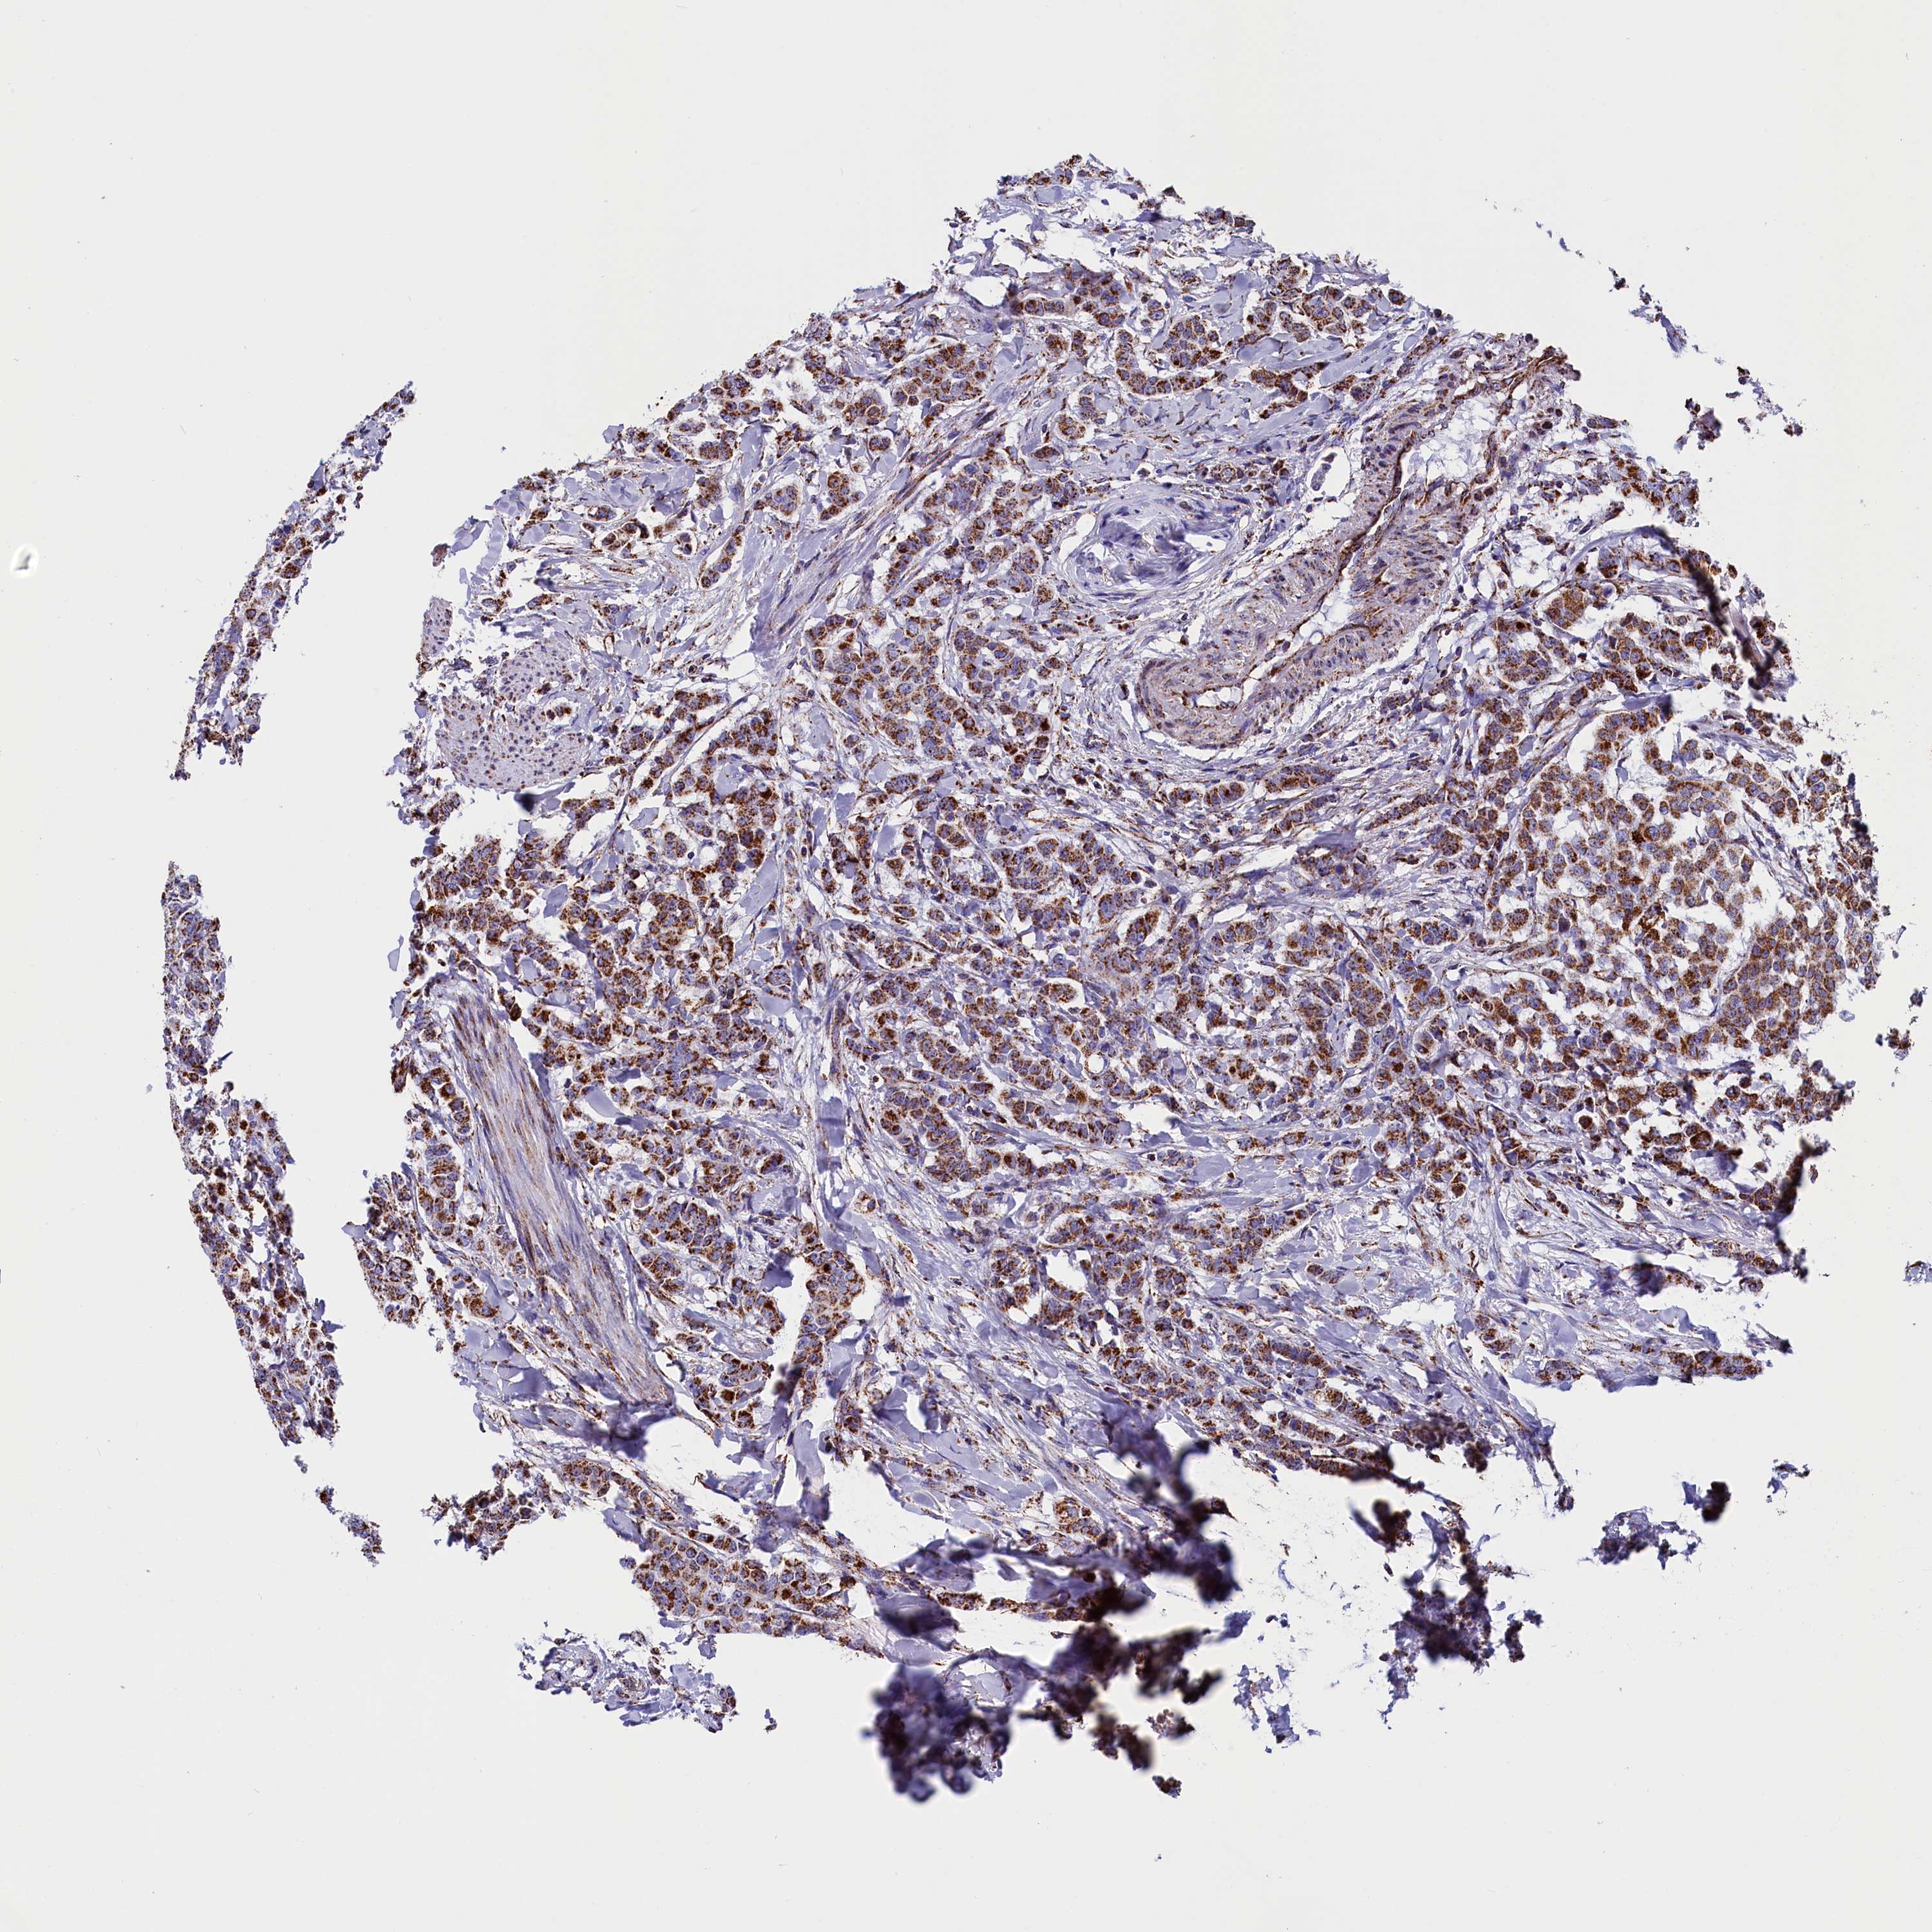

BRCA TCGA BRCA VALIDATION PROTEIN EXPRESSION

ANTIBODIES

AND

VALIDATION